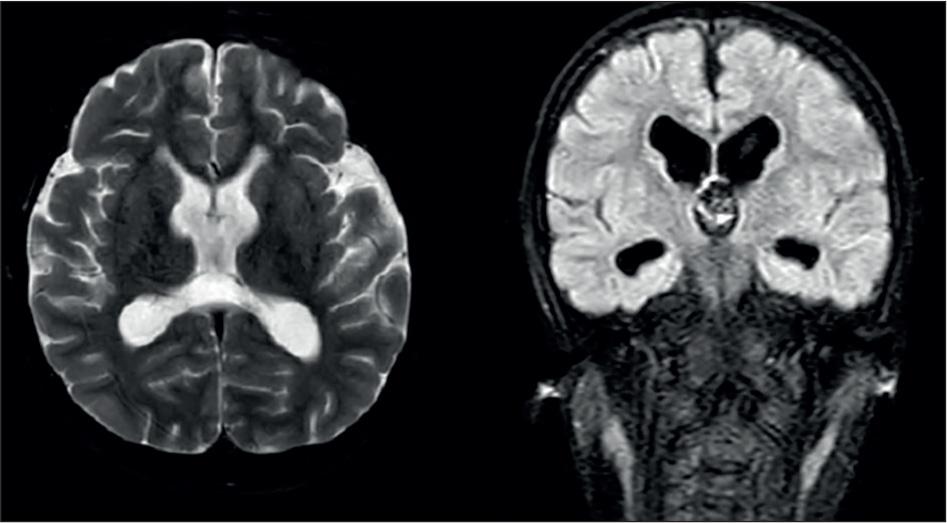

Figure 2.

Axiel T2 and Coronal T2 flair Cranial MRI images of the patient showed a thin corpus callosum, ventriculomegaly, and white matter atrophy.